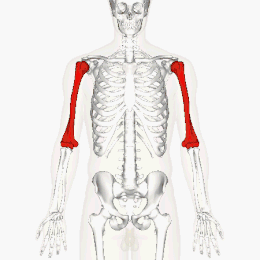

L'humérus (du latin humerus, « épaule ») est un os pair et asymétrique du membre supérieur. Il constitue le squelette du bras (entre l'épaule et le coude). C'est un os long constitué d'une diaphyse et de deux épiphyses qui s'articulent en haut avec la scapula par l'articulation gléno-humérale, et en bas avec les deux os de l'avant-bras, l'ulna et le radius par les articulations huméro-ulnaire et huméro-radiale.